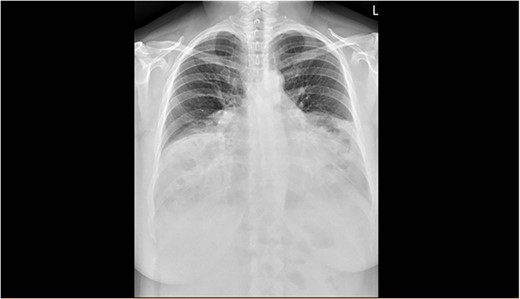

The spirometry results from her General Practitioner showed a restrictive pattern with FVC of 2.08L (55% predicted), FEV1 of 1.62L (54% predicted) and FEV1/FVC ratio of 0.78 (96% predicted). Her chest X-ray demonstrated a large hiatus or congenital hernia (Fig. 1). Subsequent computed tomography (CT) of the chest, abdomen and pelvis showed a large 88 × 48-mm defect of the anterior diaphragm consistent with MH. Hernial contents extended to the superior mediastinum and were primarily large bowel and omentum, with no intestinal obstruction (Figs 2–4).

Arterial contrast CT of the chest. Coronal slice transecting the midpoint of the chest cavity showing herniation of large bowel, small bowel and omentum into the chest cavity.